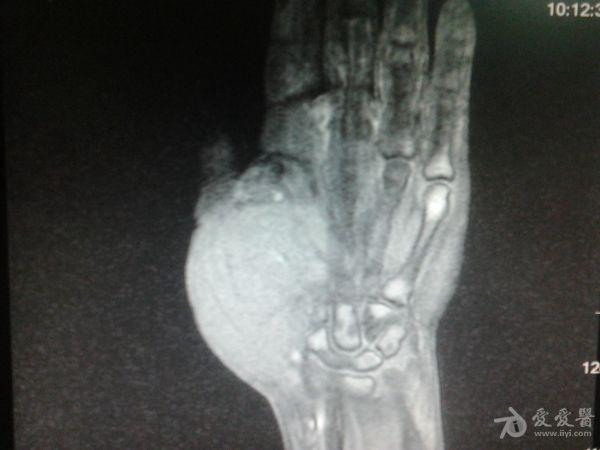

右第一掌骨、大多角骨肿瘤

男性患者,81岁,右手肿痛3个多月。无任何其它症状。体查:右手第一掌骨部肿胀明显,第一指活动受限,余四指活动可,腕关节活动小部分受限,活动时会痛。影像学检查如下。活检示:弥漫性大B细胞淋巴瘤。大家看看需不需要截肢?现在有人主张手术;有人主张不手术,直接化疗。大家有什么看法?

从以上资料看已经影响到腕关节了,还是截吧,不能姑息